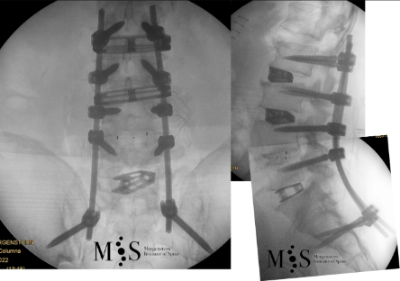

En aquests casos la cirurgia està indicada per corregir la deformitat i sobre tot per alleujar el dolor causat per l’escoliosi degenerativa. En els casos més severs d’escoliosi fins i tot pot ser necessari realitzar una osteotomía (tallar parcialment una vèrtebra) per poder redreçar la columna vertebral deformada del pacient.

Al Morgenstern Institute of Spine, utilitzem tècniques quirúrgiques endoscòpiques i percutànies per corregir les escoliosis degeneratives i permetre que el pacient es recuperi el més aviat possible. L’alta hospitalària es sol donar als pocs dies de la cirurgia.